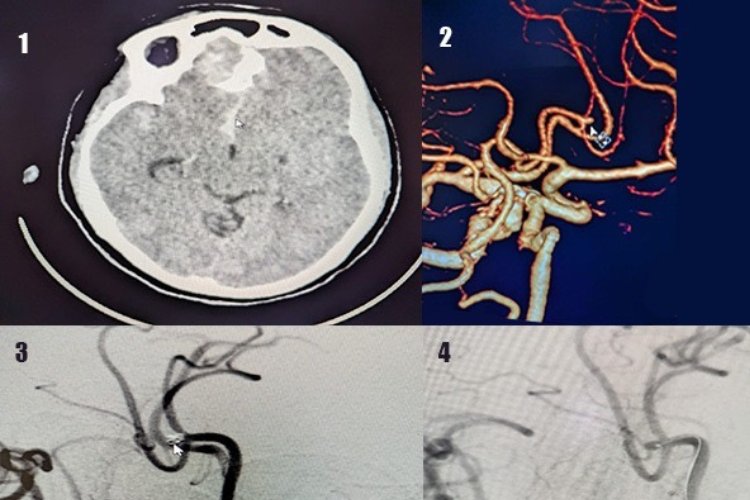

Diagnosis of brain aneurysms typically involves imaging techniques such as CT scans, MRI scans, or angiograms. These tests allow healthcare professionals to visualize the blood vessels and identify any abnormalities.